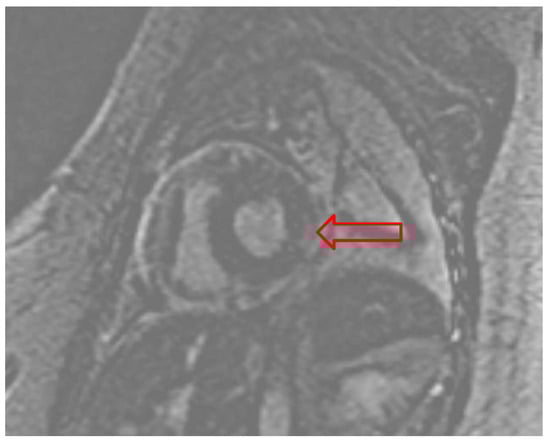

Due to suspicion of fulminant myocarditis causing cardiogenic shock, the patient underwent RV endomyocardial biopsy (EMB). A 7.5 French bioptome was inserted into the sheath with five RV biopsy specimens obtained. Histopathology results were negative for myocarditis (evaluated with CD3, CD20, and CD68 immunohistochemical staining), but cardiac magnetic resonance imaging (cMRI) reported diffuse patchy myocardial edema along the inferolateral LV wall with minimal patchy sub-epicardial delayed enhancement consistent with myocarditis (Figure 3).

Figure 3. Gadolinium enhanced cardiac MRI pointing to the patchy sub-epicardial delayed enhancement of the basal lateral/inferolateral wall (red arrow).

Our patient had a typical presentation with viral prodrome symptoms preceding respiratory symptoms that quickly progressed to hemodynamic instability initially due to tamponade but ultimately due to cardiogenic and distributive shock. Point of care ultrasound (POCUS) is a valuable tool for establishing the diagnosis in hemodynamically unstable patients, as it can rapidly differentiate the type of shock [12]. Formal TTE is also often necessary to evaluate ventricular function and pericardial morphology [13,14]. In our patient, LV dysfunction with increased concentric wall thickness resembling myocardial hypertrophy was an unusual finding in a young individual without prior cardiac history or hypertension. The etiology was suspected to be myocardial edema due to acute influenza infection, which was later confirmed on cMRI. Despite the cMRI revealing minimal patchy sub-epicardial delayed enhancement, the RV EMB was negative for myocarditis. False negative biopsy results, however, are not uncommon, mainly due to sampling error [15]. The sub-epicardial location of the inflammation also likely contributed to the negative RV EMB.